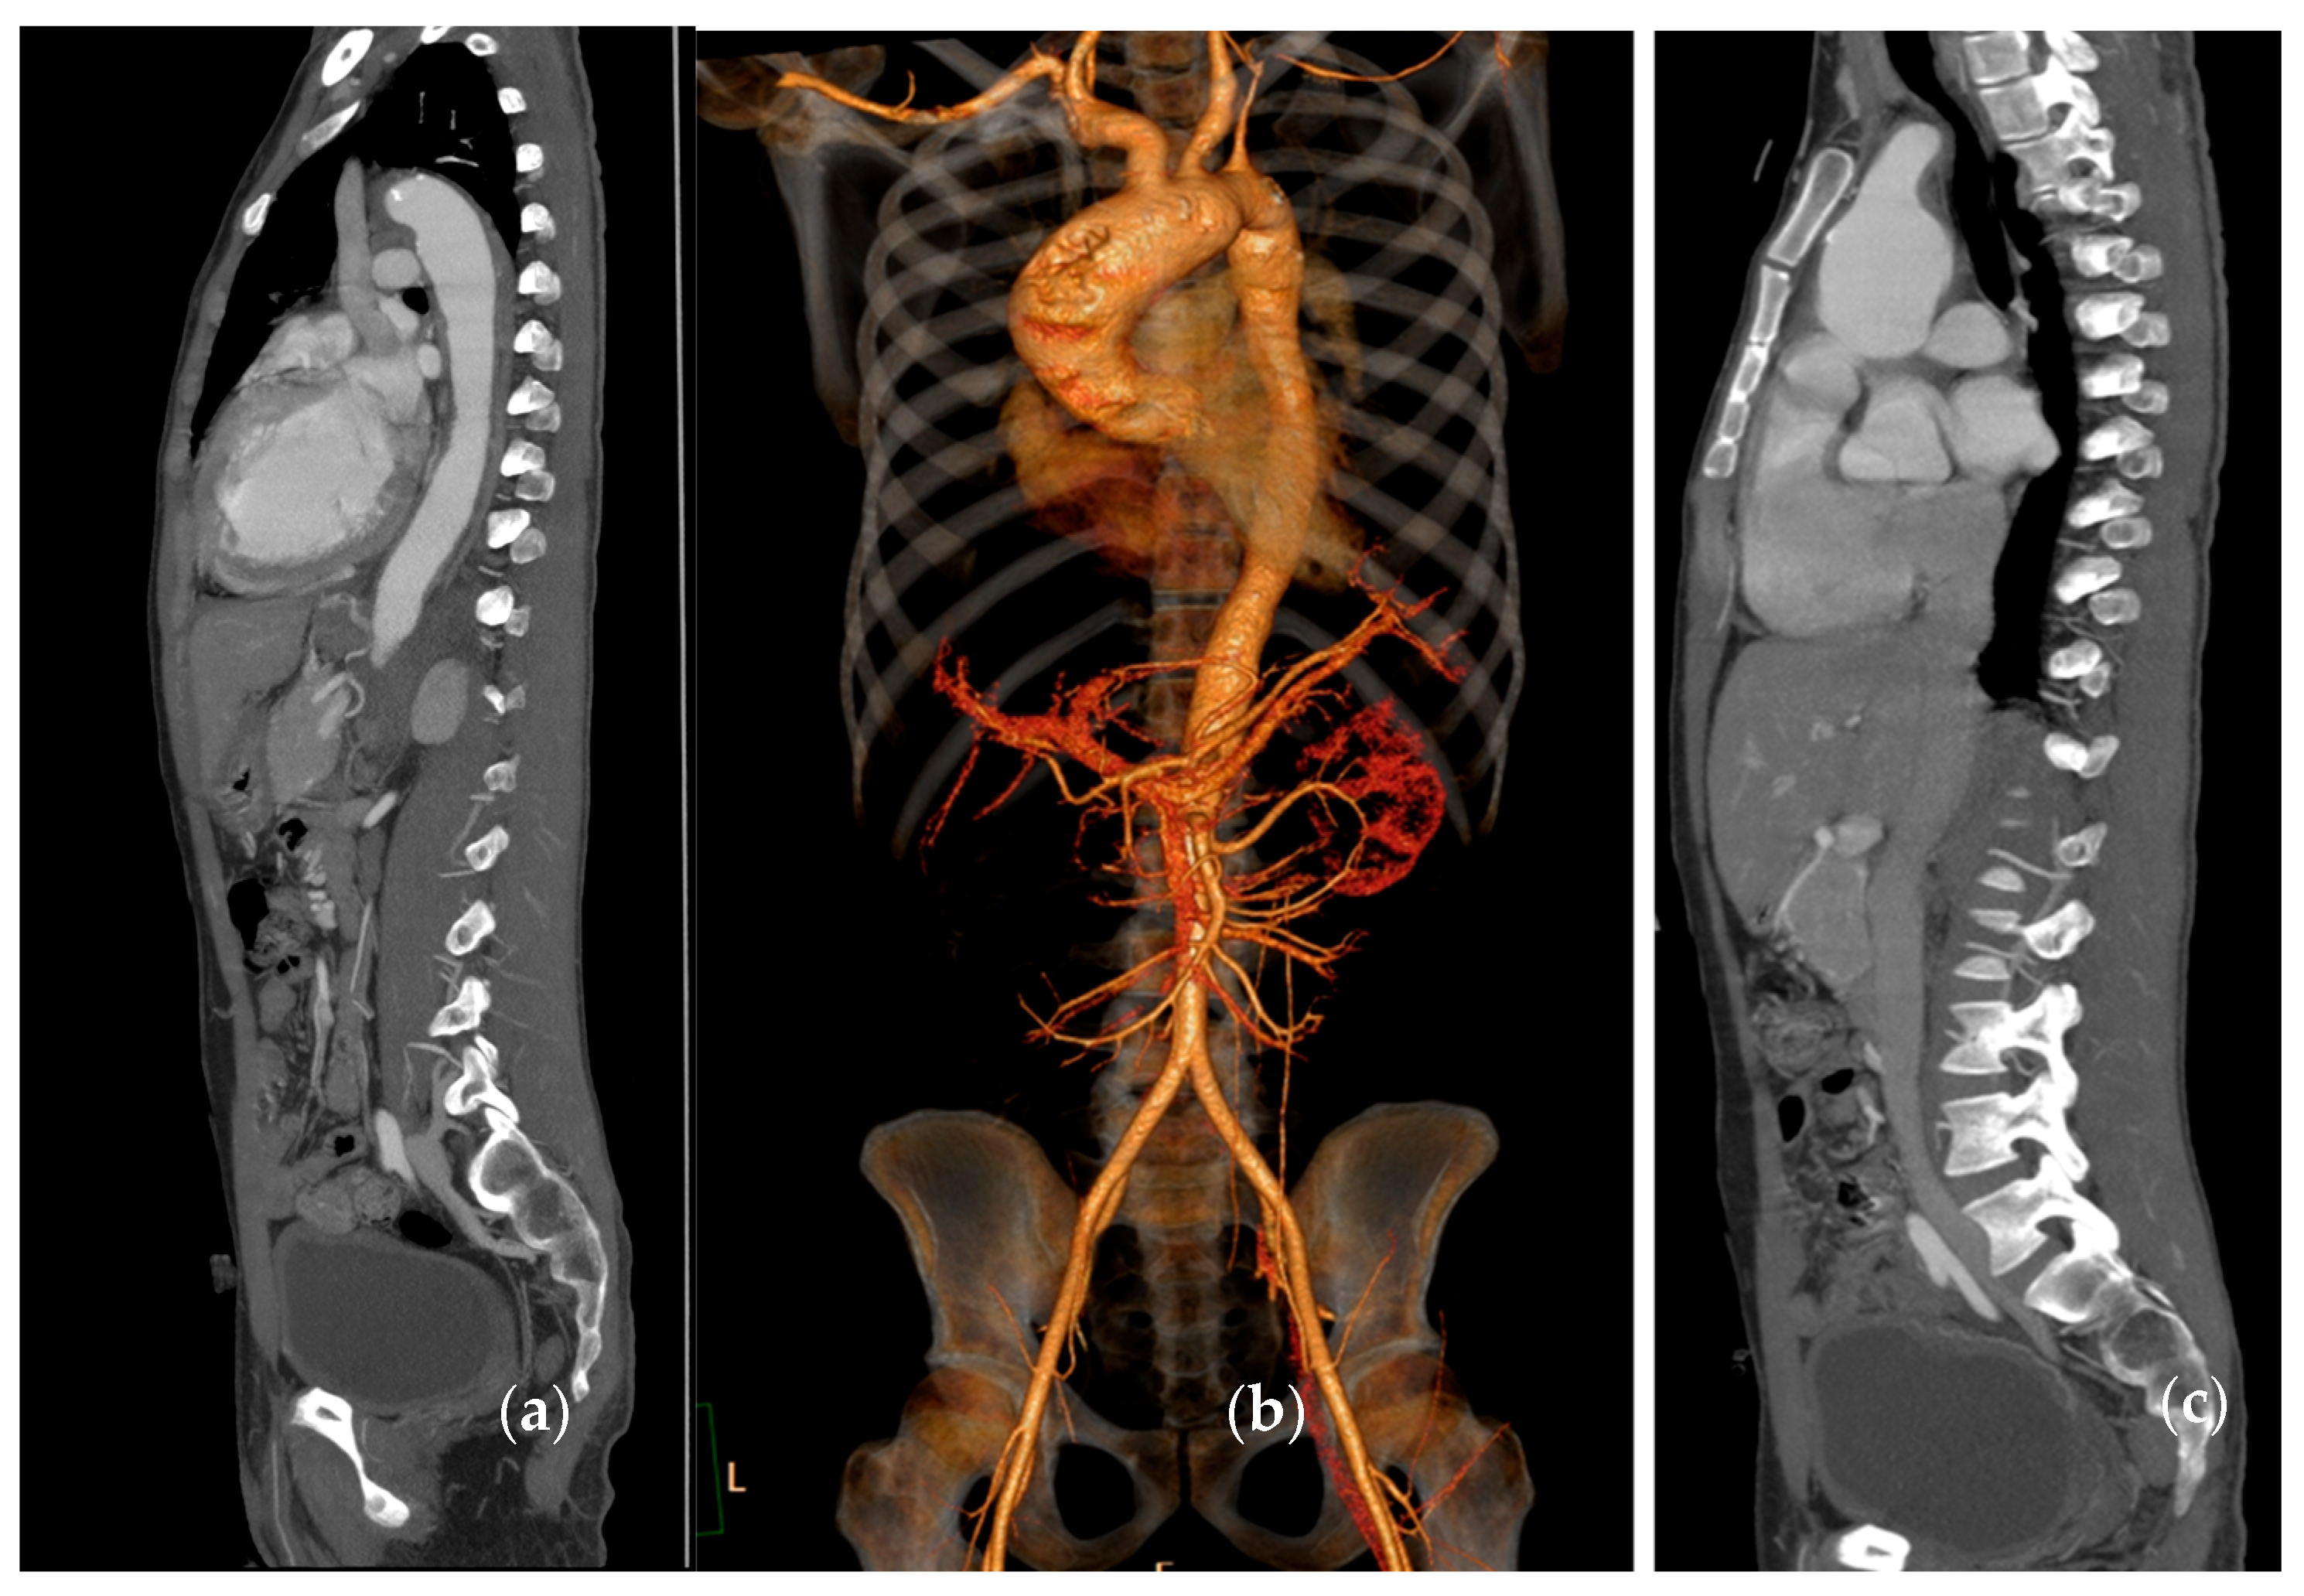

5. Computed Tomography (CT)/CT Angiography

5.2. Takayasu Arteritis